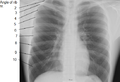

X-ray image of human chest, with ribs labeled.